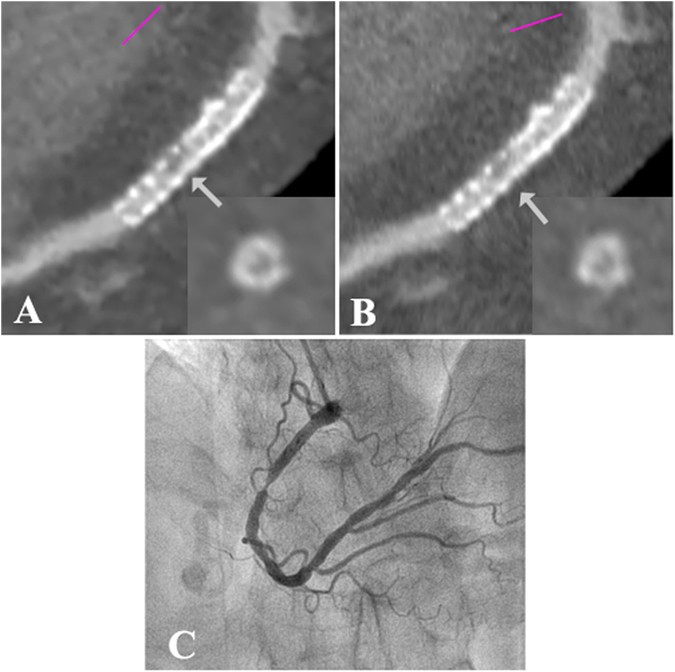

Iterative Reconstruction Improves Detection Of In Stent Restenosis By High Pitch Dual Source Coronary Ct Angiography Scientific Reports

www.nature.com

Plos One Coronary Stent Artifact Reduction With An Edge Enhancing Reconstruction Kernel A Prospective Cross Sectional Study With 256 Slice Ct

journals.plos.org